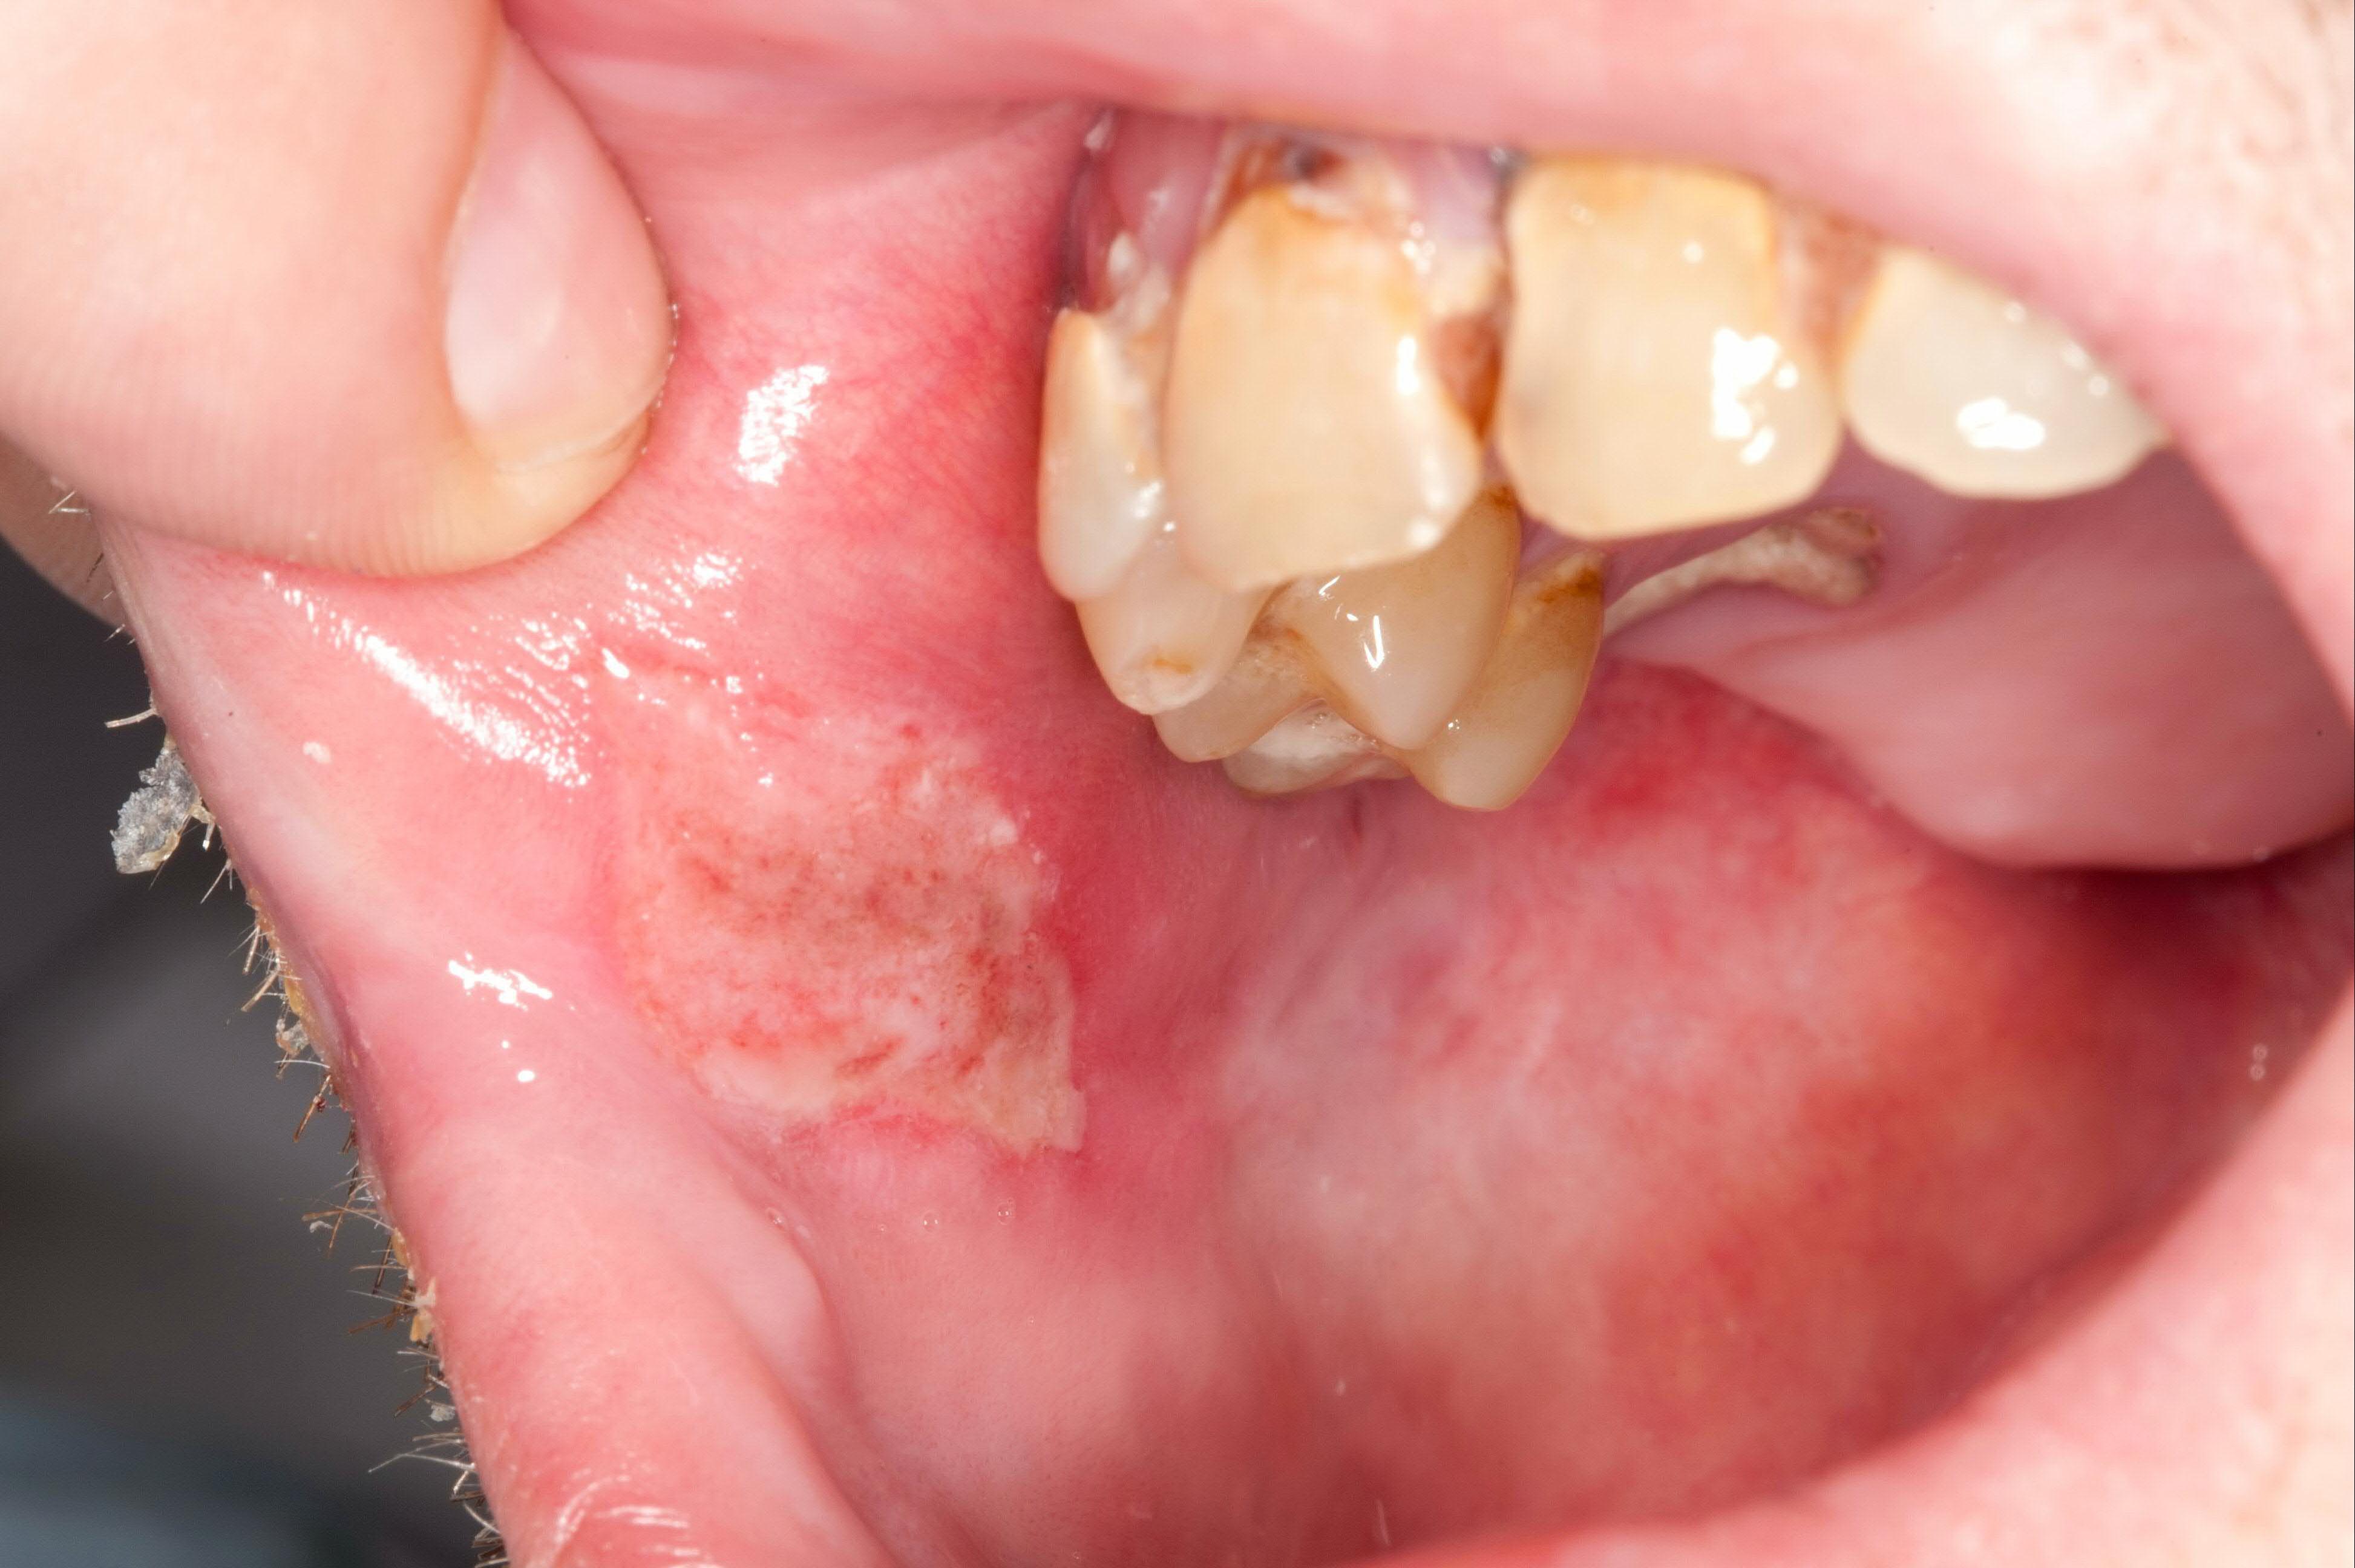

What it looks like

- Color: white, lace-like patterns with red erosive ulcers

- Shape: linear or irregular

- Texture: rough, leathery, sometimes ulcerated

The classic “lacy” white pattern (reticular lichen planus).

Erosive or ulcerative lichen planus can look red and raw.

Why it matters

It can be long-term and needs monitoring. There is a small risk of malignant transformation, so persistent or changing lesions should be followed by a clinician.